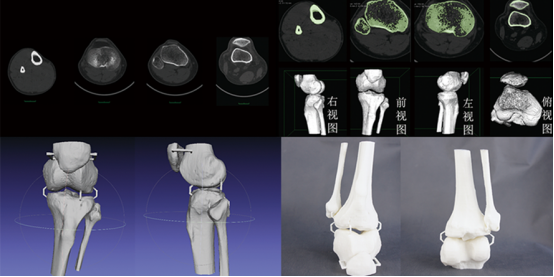

首先,医生通过CT扫描获取了张先生胫骨的详细数据,并利用3D打印技术打印出了精确的骨折模型。这个模型不仅帮助医生更好地了解了骨折的形态和位置,还为手术方案的制定提供了重要参考。

接着,医生根据骨折模型设计并打印出了与患者骨骼完美匹配的骨折固定板。在手术过程中,医生将固定板精确地植入到骨折部位,并使用螺钉进行固定。由于固定板与患者骨骼完美契合,手术过程非常顺利,且术后恢复效果良好。